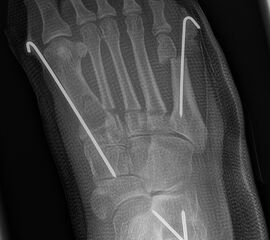

Zusätzlich schränken Wachstumsfugen die Wahl der Osteosynthese ein. Eine die Fuge kreuzende Osteosynthese ist ausschließlich mit Kirschner-Drähten möglich (Abb. 3).

Abb. 3 a-j: Beispiel einer Calcaneusverschiebeosteotomie mit offenen Wachstumsfugen und der entsprechenden Osteosynthese mit Kirschner Drähten. Lokalisation der Osteotomie (a), Lage der Fräse (b-d), Drahtlage mehrere Ansichten (e-h), Heilung der Osteotomie 4 Wochen postoperativ und Entfernung der Drähte (i-j).

Calcaneus-Osteotomie

Die minimalinvasive Calcaneusverschiebeosteotomie bietet eindeutige Vorteile gegenüber dem offenen Verfahren, sodass wir bei Kindern und Jugendlichen nahezu keine offene Verschiebeosteotomie mehr durchführen. Am Calcaneus liegt die offene Wachstumsfuge dorsal. Bei der Durchführung müssen Schenkel der V-förmigen Osteotomie daher etwas steiler angelegt werden, in einem stumpfen Winkel (siehe Abb. 3 a-j). Für die Osteotomie liegen unsere Patienten auf dem Rücken und der BV wird für die exakte Seitaufnahme eingestellt. Der Fuß lagert auf einem hohen OP-Kissen und die Osteotomie kann bequem mit einem langen Kirschner-Draht und einem sterilen Stift angezeichnet werden (Abb. 15).